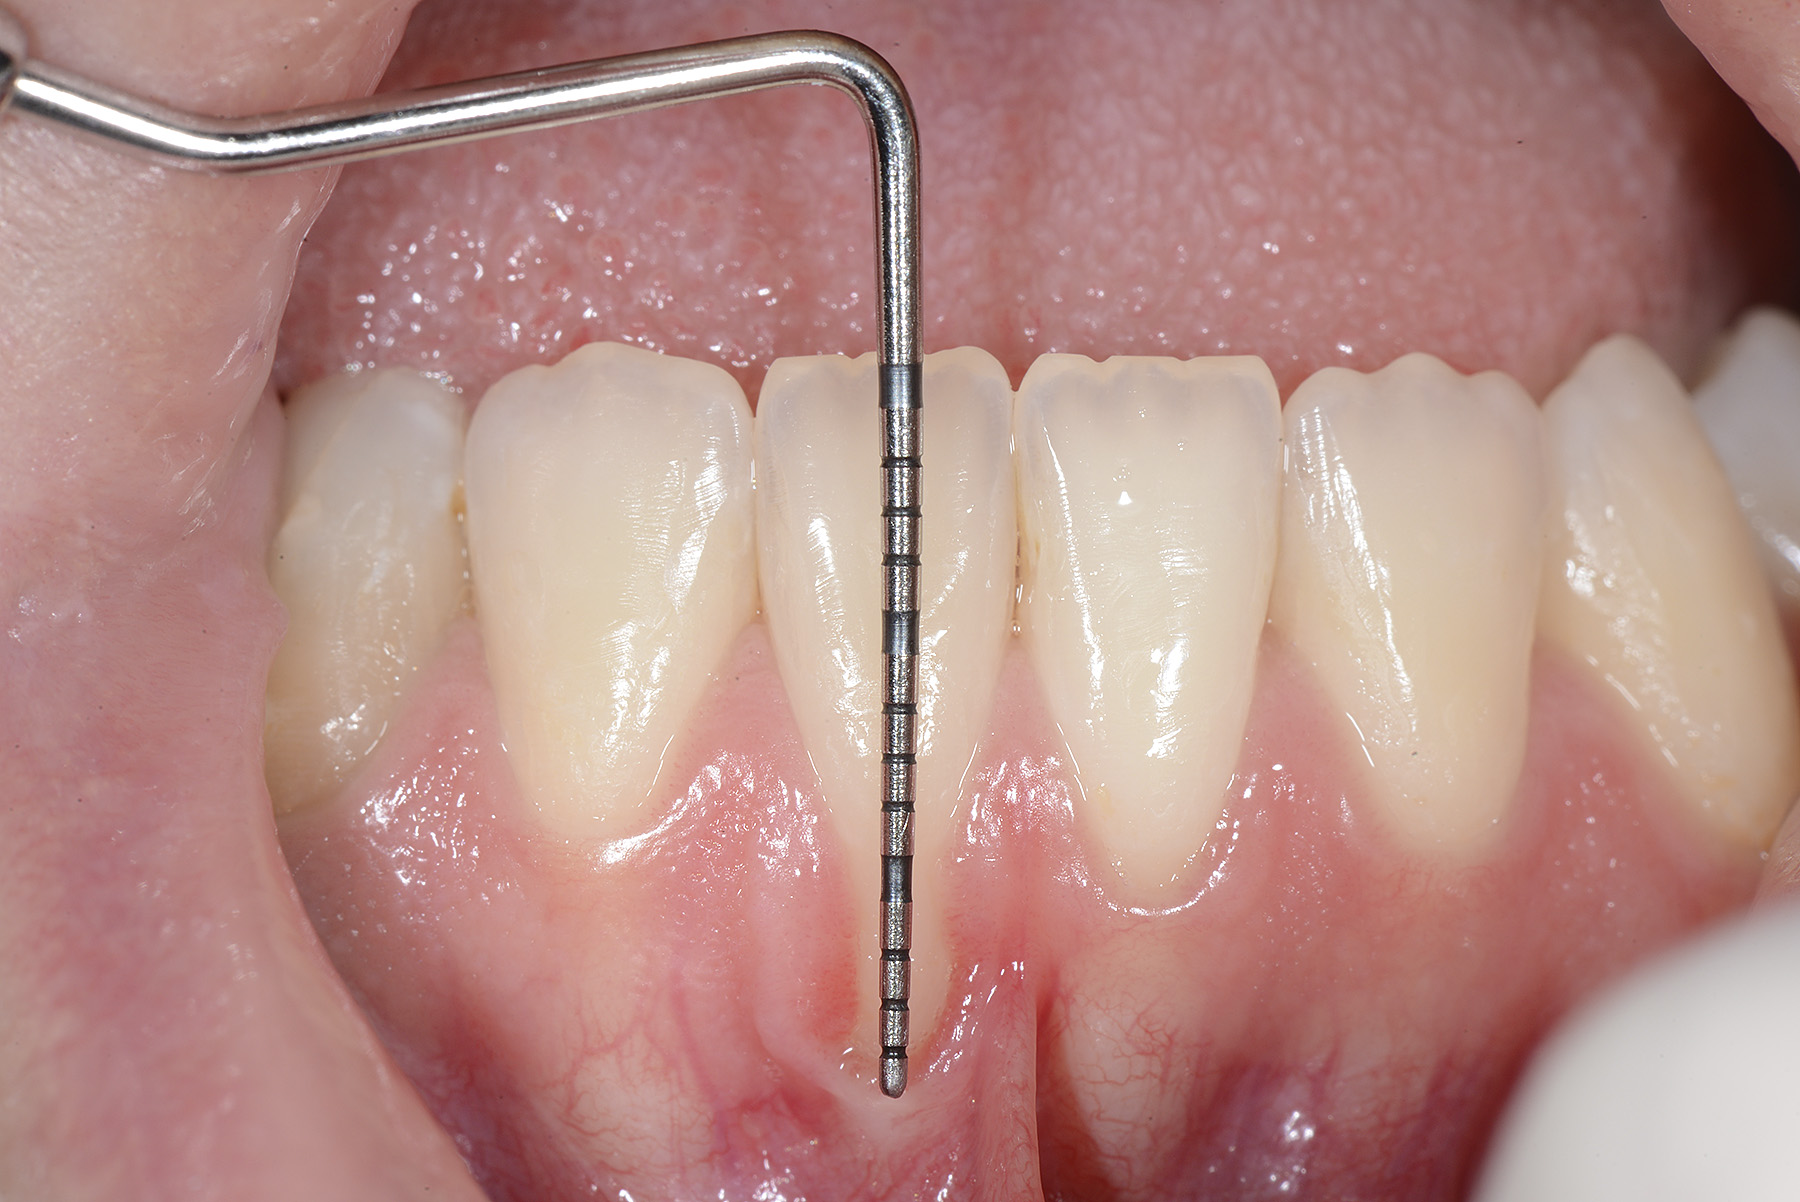

PREMESSA: in seguito all’estrazione dell’incisivo laterale superiore di destra, resasi necessaria per cause batteriche, si decide di affrontare il caso con il posizionamento di un impianto in sostituzione dell’elemento mancante dopo guarigione del sito infetto. Con tecniche rigenerative sia dei tessuti ossei mancanti a causa dell’infezione pregressa, sia dei tessuti gengivali che appaiono inizialmente troppo spostati in alto, si ripristina una corretta morfologia delle parabole (contorni) gengivali e delle papille interdentali (triangoli di gengiva tra due denti vicini).